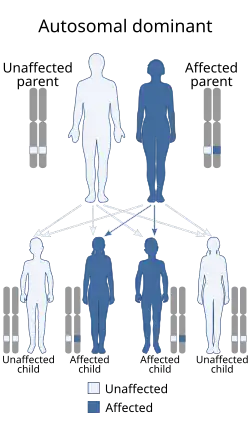

Синдром Ди Георга (синдром Ди Джорджа, синдром Ди Джорджи, синдром дисэмбриогенеза 3-4 жаберной дуги, врождённая аплазия тимуса и паращитовидных желёз, синдром 22q11.2, CATCH 22 phenotype[2]) — разновидность идиопатического изолированного гипопаратиреоза; редкое врождённое заболевание. Генетической причиной синдрома Ди Георга является делеция центрального участка длинного плеча хромосомы 22 (22q11.2) размером 1,5—3 млн.п.н. Однако известны случаи, когда при тех же клинических проявлениях имеет место делеция других хромосом — 10р13, 17р13, 18q21 и других. В большинстве случаев делеция происходит во время мейоза при спермато- или овогенезе. Только в 5—10 % случаев дефектная хромосома наследуется по аутосомно-доминантному типу[3]. Характеризуется агенезией или дисгенезом паращитовидных (околощитовидных) желёз, аплазией тимуса (вилочковой железы), приводящей к резкому снижению популяции Т-лимфоцитов и иммунологической недостаточности, врождёнными аномалиями крупных сосудов (дефекты аорты, тетрада Фалло)[4].

Заболевание развивается в результате повреждения закладки 3—4-го жаберных карманов, в результате которого нарушается закладка паращитовидных желёз и тимуса. Тип наследования до конца не установлен — некоторые авторы предполагают аутосомно-доминантный тип с различной экспрессивностью[6].